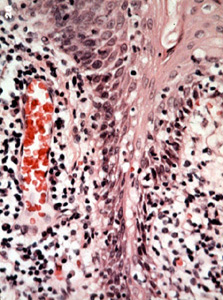

Este microfotografía muestra  la configuración de las papilas. Hay numerosos dedos, como proyecciones cubiertas por epitelio escamoso respaldados por centros de conjuntivo que contiene inflamación crónica.

Note las numerosas células inflamatorias en el tejido conjuntivo y los vasos sanguíneos notablemente dilatados.

A mayor poder de resolución se observa  la reacción inflamatoria  compuesta por linfocitos y plasmocitos. Pero no se observa ninguna displasia en el epitelio.